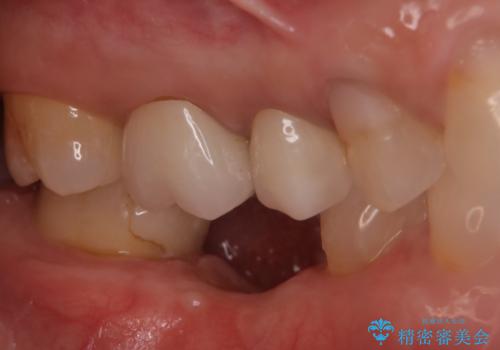

『インプラント』主訴:歯を入れたい

- 他院で抜歯されて、今後どうしたらいいのかを相談された患者様です。

抜歯を行った後は、Br、義歯、インプラント、何もしないという選択肢のメリットデメリットを説明させていただき患者様がインプラント治療を希望されたので今回治療させていただくことになりました。

二回の手術を終えて最終的な被せ物が入るまで6〜8ヶ月かかると思います。

歯のなかったところをインプラント治療を行うことによってまた噛める喜びを感じていただけて良かったと思っております。